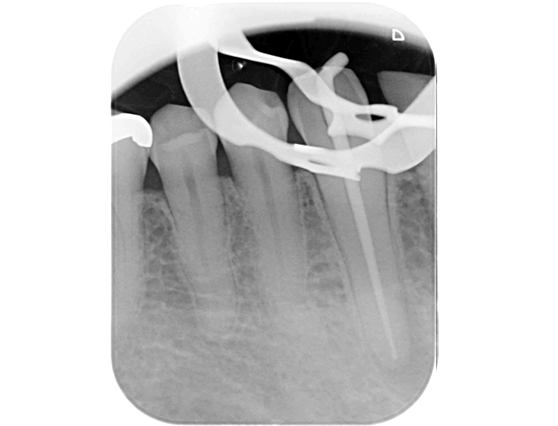

根管治療 症例7

治療中